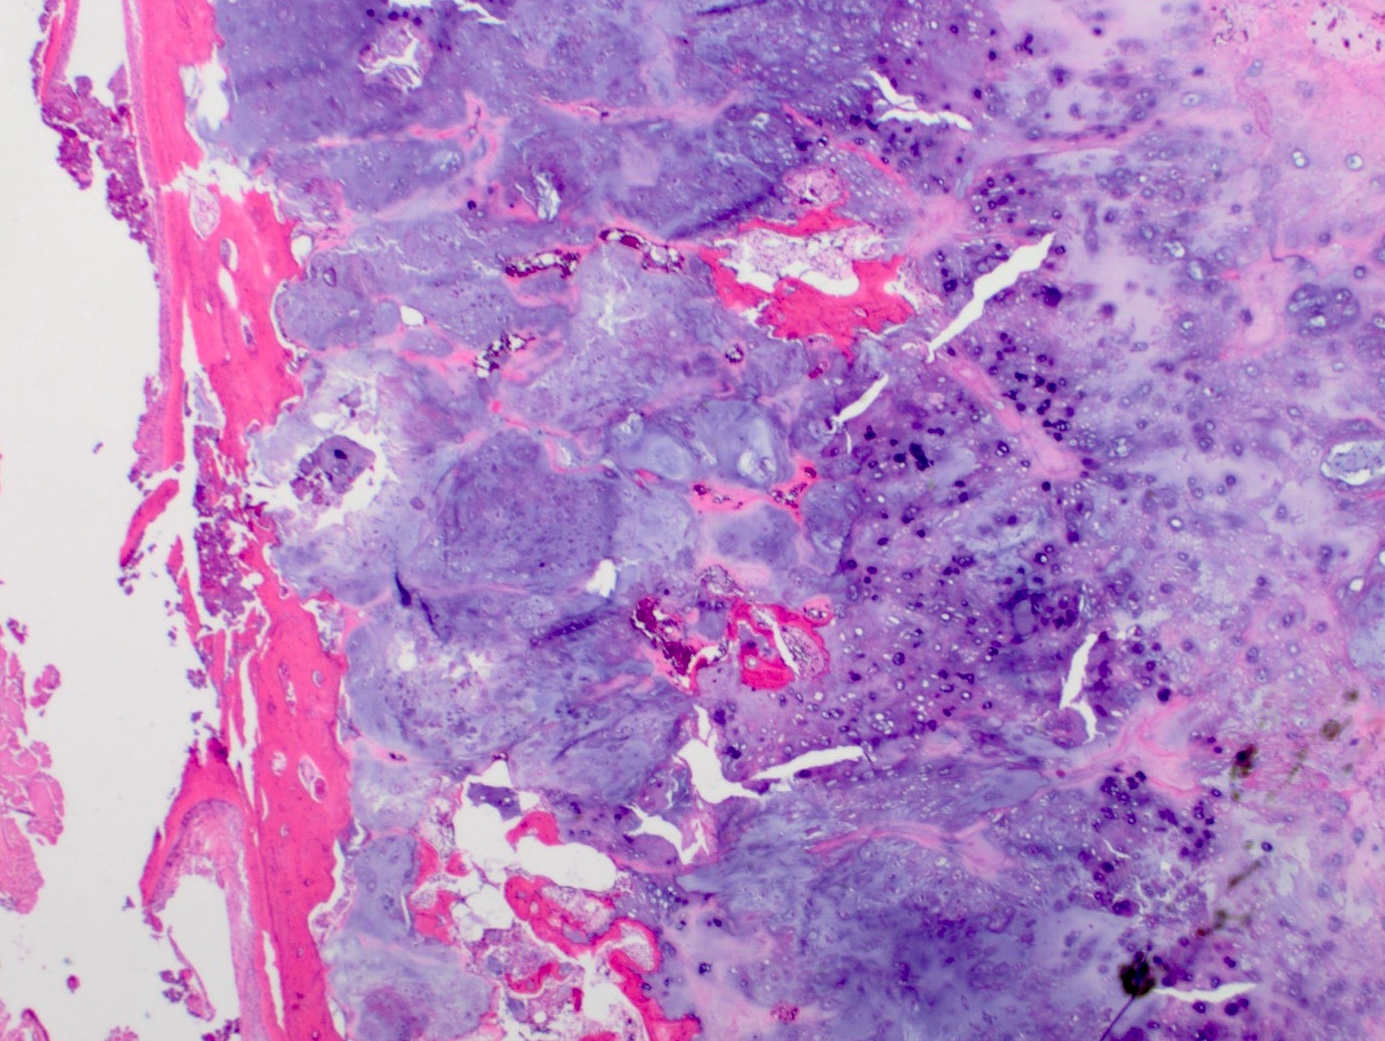

Microscopic (histologic) description

- Lobulated growth pattern (J Dent Res Dent Clin Dent Prospects 2011;5:98)

- Lobules have irregular shapes and sizes and may be separated by fibrous bands containing small vessels (Virchows Arch 2012;460:95)

- Lobules are composed of abundant hyaline cartilage matrix (sometimes with mucoid / myxoid changes) and permeate and entrap lamellar bone trabeculae

- Cellularity is slightly higher than in enchondroma

- Cells show moderate eosinophilic to vacuolated cytoplasm

- Nuclei are small and uniform with condensed chromatin (lymphocyte-like); sometimes they show open chromatin with visible nucleoli (Am J Surg Pathol 2009;33:50)

- Mitoses and significant nuclear pleomorphism are absent

- Binucleation can be observed

- Necrosis can be seen

- In cases arising from pre-existing enchondromas, areas of enchondroma with calcifications can be present

Microscopic (histologic) images

- Microscopic description: Examination of the histopathologic sections reveals mature trabecular bone with juxtaposed cartilaginous proliferation, characterized by low to moderate cellularity, chondrocytes with occasional binucleated cells and mild atypia in a hyaline cartilage matrix. Foci of necrosis, nonischemic type are seen. Given the presence of nonischemic type necrosis, the large size of the tumor and the cellular atypia, the tumor is most consistent with atypical cartilaginous tumor that may have arisen from an osteochondroma.